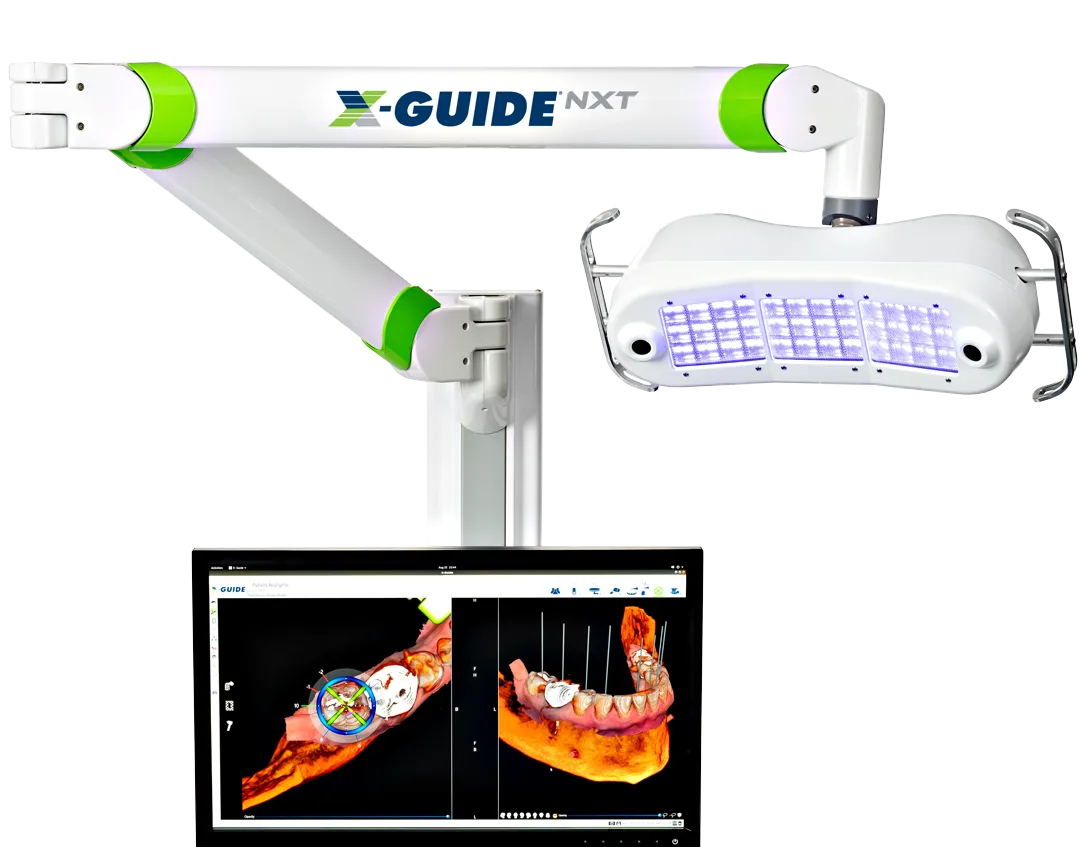

Dynamic 3D Navigation for Implant Precision

Now featuring PrecisionArch™ — a guided system for safer, more precise implant placement.

At Chippewa Creek Dental, we bring digital planning to life in real time, so you get safer, more precise implant placement.

Thanks to Dynamic 3D Navigation technology, we can control the exact position, angle, and depth of your implant with pinpoint accuracy. This system has been shown to be significantly more accurate than traditional freehand surgery, giving you a higher level of safety and predictability.

This level of precision means fewer incisions, less discomfort, and a faster healing experience, helping you get back to normal life sooner.

It’s an advanced approach that allows us to deliver safe, predictable, natural-looking results, all in a single visit.

Dynamic Navigation 11X more accurate than freehand implant surgery.

A Perfect Smile With 3D Digital Imaging

PrecisionArch™ Gives You Greater Precision, Faster Surgery, Faster Recovery!

By using the latest 3D digital imaging technology and a fully digital workflow, we can plan and place your implants with far greater precision, so you get safer, more predictable results.

This advanced scanner captures detailed images of your teeth, gums, bone, and facial structure. With this information, we’re able to design a treatment plan that fits you perfectly and ensures your implants are positioned exactly where they need to be.

This way, your smile will be exactly how it was meant to look.

Many dentists only use a CBCT scanner, but not many use this new technology. We are one of the FEW Centers in North East Ohio using Photogrammetry technology.